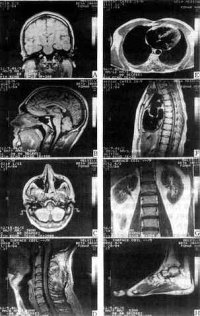

不同器官结构的MRI

MRI提供的信息量不但大于医学影像学中的其他许多成像术,而且不同于已有的成像术,因此,它对疾病的诊断具有很大的潜在优越性。它可以直接作出横断面、矢状面冠状面和各种斜面的体层图像,不会产生CT检测中的伪影;不需注射造影剂;无电离辐射,对机体没有不良影响。MRI对检测脑内血肿、脑外血肿脑肿瘤颅内动脉瘤、动静脉血管畸形、脑缺血椎管内肿瘤、脊髓空洞症脊髓积水等颅脑常见疾病非常有效,同时对腰椎椎间盘后突、原发性肝癌等疾病的诊断也很有效。

1. 头部。可清晰分辨脑灰质和白质,对多发性硬化等一类脱髓鞘病优于CT。对脑外伤、脑出血脑梗塞脑肿瘤等同CT类似,但可显示CT为等密度的硬膜下血肿。脑梗塞或脑肿瘤的早期,CT不能查出,而MRI有可能显示。对钙化脑膜瘤显示不好。脑干小脑病变的MRI图像由于没有伪影是首选检查方法。

2. 脊柱。不需要造影剂就能清晰区分脊髓、硬膜囊和硬膜外脂肪。对肿瘤脊髓空洞症、脱髓鞘病变等均有较高诊断价值。显示骨折脱位不如常规X射线或CT,但能观察脊髓损伤情况。显示椎间盘较好,可以分辨纤维环髓核,特别是矢状面图像可以同时显示多个椎间盘突出。

3. 四肢。对骨质本身病变显示不如常规X射线或CT。对软组织及肌肉病变包括肿瘤及炎症都能清晰显示,特别是对早期急性骨髓炎,是一种灵敏度很高的检查方法。也是检查膝关节半月板病变的首选方法。

5. 胸部。对肺的检查不如常规X射线,对纵隔检查则优于CT,不用造影剂即可分辨纵隔血管和肿物,也是一项有价值的心血管检查技术。

6. 腹部。主要用于肝、胰、脾、肾等实质脏器。